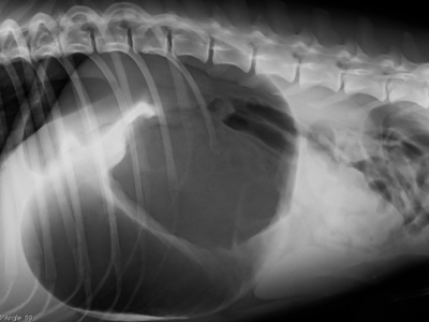

Notfall Magendrehung

Die Magendrehung ist eine seltene, aber schwerwiegende und lebensbedrohliche Notfallsituation von grossen Hunderassen.